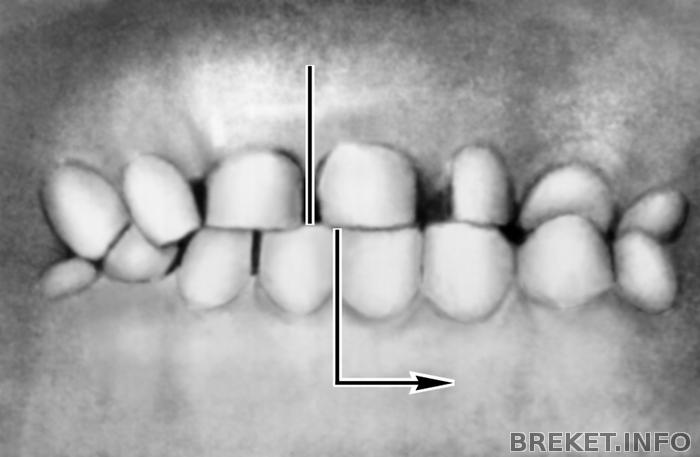

Вот картинки по перекрестному прикусу. У меня тоже если присмотреться подбородок нессиметричен и ноздря одна как будто бы больше )) вот как у этой девушке на фото - очень похоже.

В том то и дело что уздечки эти у меня строго на месте и на нижней челюсти строго между единичками и на нижней строго между единичками. Но центр не сходится, так как челюсть нижняя влево уходит при смыкании. На фото этой девушке сделали операцию. Просто не все проблемы брекетами можно решить. Визуально зубы могут быть в правильном прикусе с посощью брекетов, а сам сустав (нижняя челюсть) также не правильно смыкаться и это грозит куче проблем со здоровьем. Или после брекетов профиль может измемиться и ассиметрия восстановиться?? Хорошо бы если так... Просто когда смещение нижней челюсти поначиталась и проблемы с дыханием и глотанием могут быть и воспаление нервов зубов и проблемы с деснами... ((( Просто меня удивляет почему тот орт смотрел и долго пытался понять как у меня смыкается челюсть и предупредил что нужна операция бы, а второй просто не смотрел как я смыкаю зубы, а наклеил брекеты и делов. Не хочу обижаться на своего орта...но почему моя орт ничего про это не сказала??? не заметила? не захотела замечать?? а ведь правда присмотреться - у меня не симметричный подбородок... (((((( Неужели брекетами можно симметрию и овал лица изменить в нужном порядке??

У этой девушки была операция. У меня немного похоже. Но я носила еще полгода капу, чтобы сустав поставить на место, стало посимметричнее. Вам диагностику делали? Бывает, что челюсть уезжает из-за неправильного смыкания зубов, а если это случилось давно, например из-за неправильных пломб, то ветви самой нижней челюсти могли вырасти неравномерно, одна длиннее, одна короче.

Да, прикус перекрёстный.

Центр ВЧ у Вас на месте. А центр на нижней челюсти смещён на ползуба. Центр тягами исправляется,не переживайте